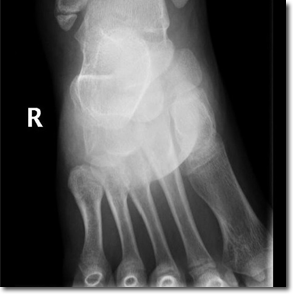

Niña de 11 años de edad sin antecedentes de interés que acude a Urgencias por dolor a nivel del maléolo externo del miembro inferior derecho tras un movimiento anómalo del pie con inversión del tobillo hace 2 días. Asocia tumefacción e impotencia funcional leves. Le han administrado analgesia en el domicilio sin mejoría. A la exploración, presenta tumefacción y dolor selectivo a la palpación del maléolo externo y los ligamentos peroneoastragalinos anterior y posterior.